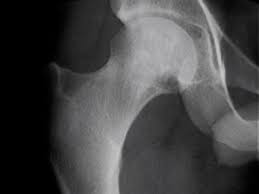

Hip Arthroscopy

Hip arthroscopy is a minimally invasive surgery where there is uses a small camera device called an arthroscope to see inside your hip joint. This allows them to diagnose issues like tears, impingement, or loose fragments, and potentially treat them with small tools inserted through other tiny cuts.